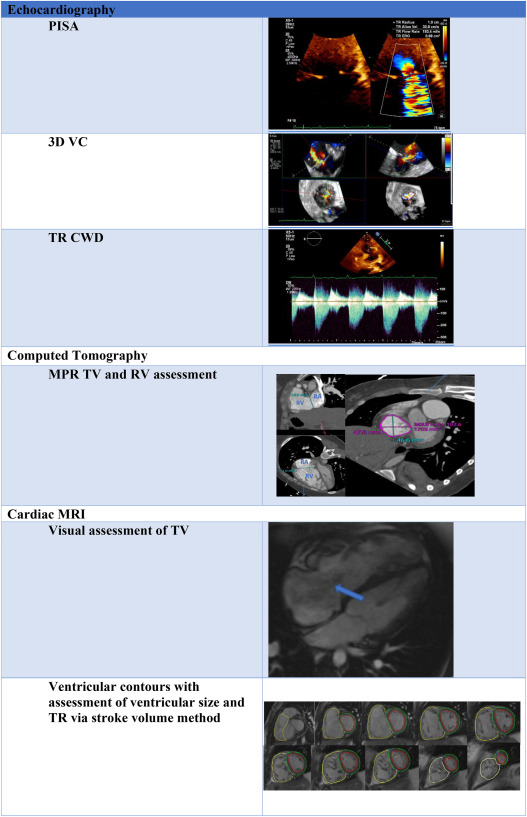

Echocardiography. 36: 954-957Hahn R.T. Thomas J.D. Khalique O.K. et al.

Imaging Assessment of Tricuspid Regurgitation Severity.

JACC Cardiovasc Imaging. 12: 469-490Badano L.P. Hahn R. Zanella H. et al.

Morphological Assessment of the Tricuspid Apparatus and Grading Regurgitation Severity in Patients With Functional Tricuspid Regurgitation: Thinking Outside the Box.

JACC Cardiovasc Imaging. 12: 652-664

The need for a new tricuspid regurgitation grading scheme.

Eur Heart J Cardiovasc Imaging. 18: 1342-1343Hahn R.T. Weckbach L.T. Noack T. et al.

Proposal for a Standard Echocardiographic Tricuspid Valve Nomenclature.

J Cardiovasc Magn Reson. 1: 7-21Sugeng L. Mor-Avi V. Weinert L. et al.

Multimodality Comparison of Quantitative Volumetric Analysis of the Right Ventricle.

J Am Coll Cardiol. 71: 2935-2956Agricola E. Asmarats L. Maisano F. et al.

Imaging for Tricuspid Valve Repair and Replacement.